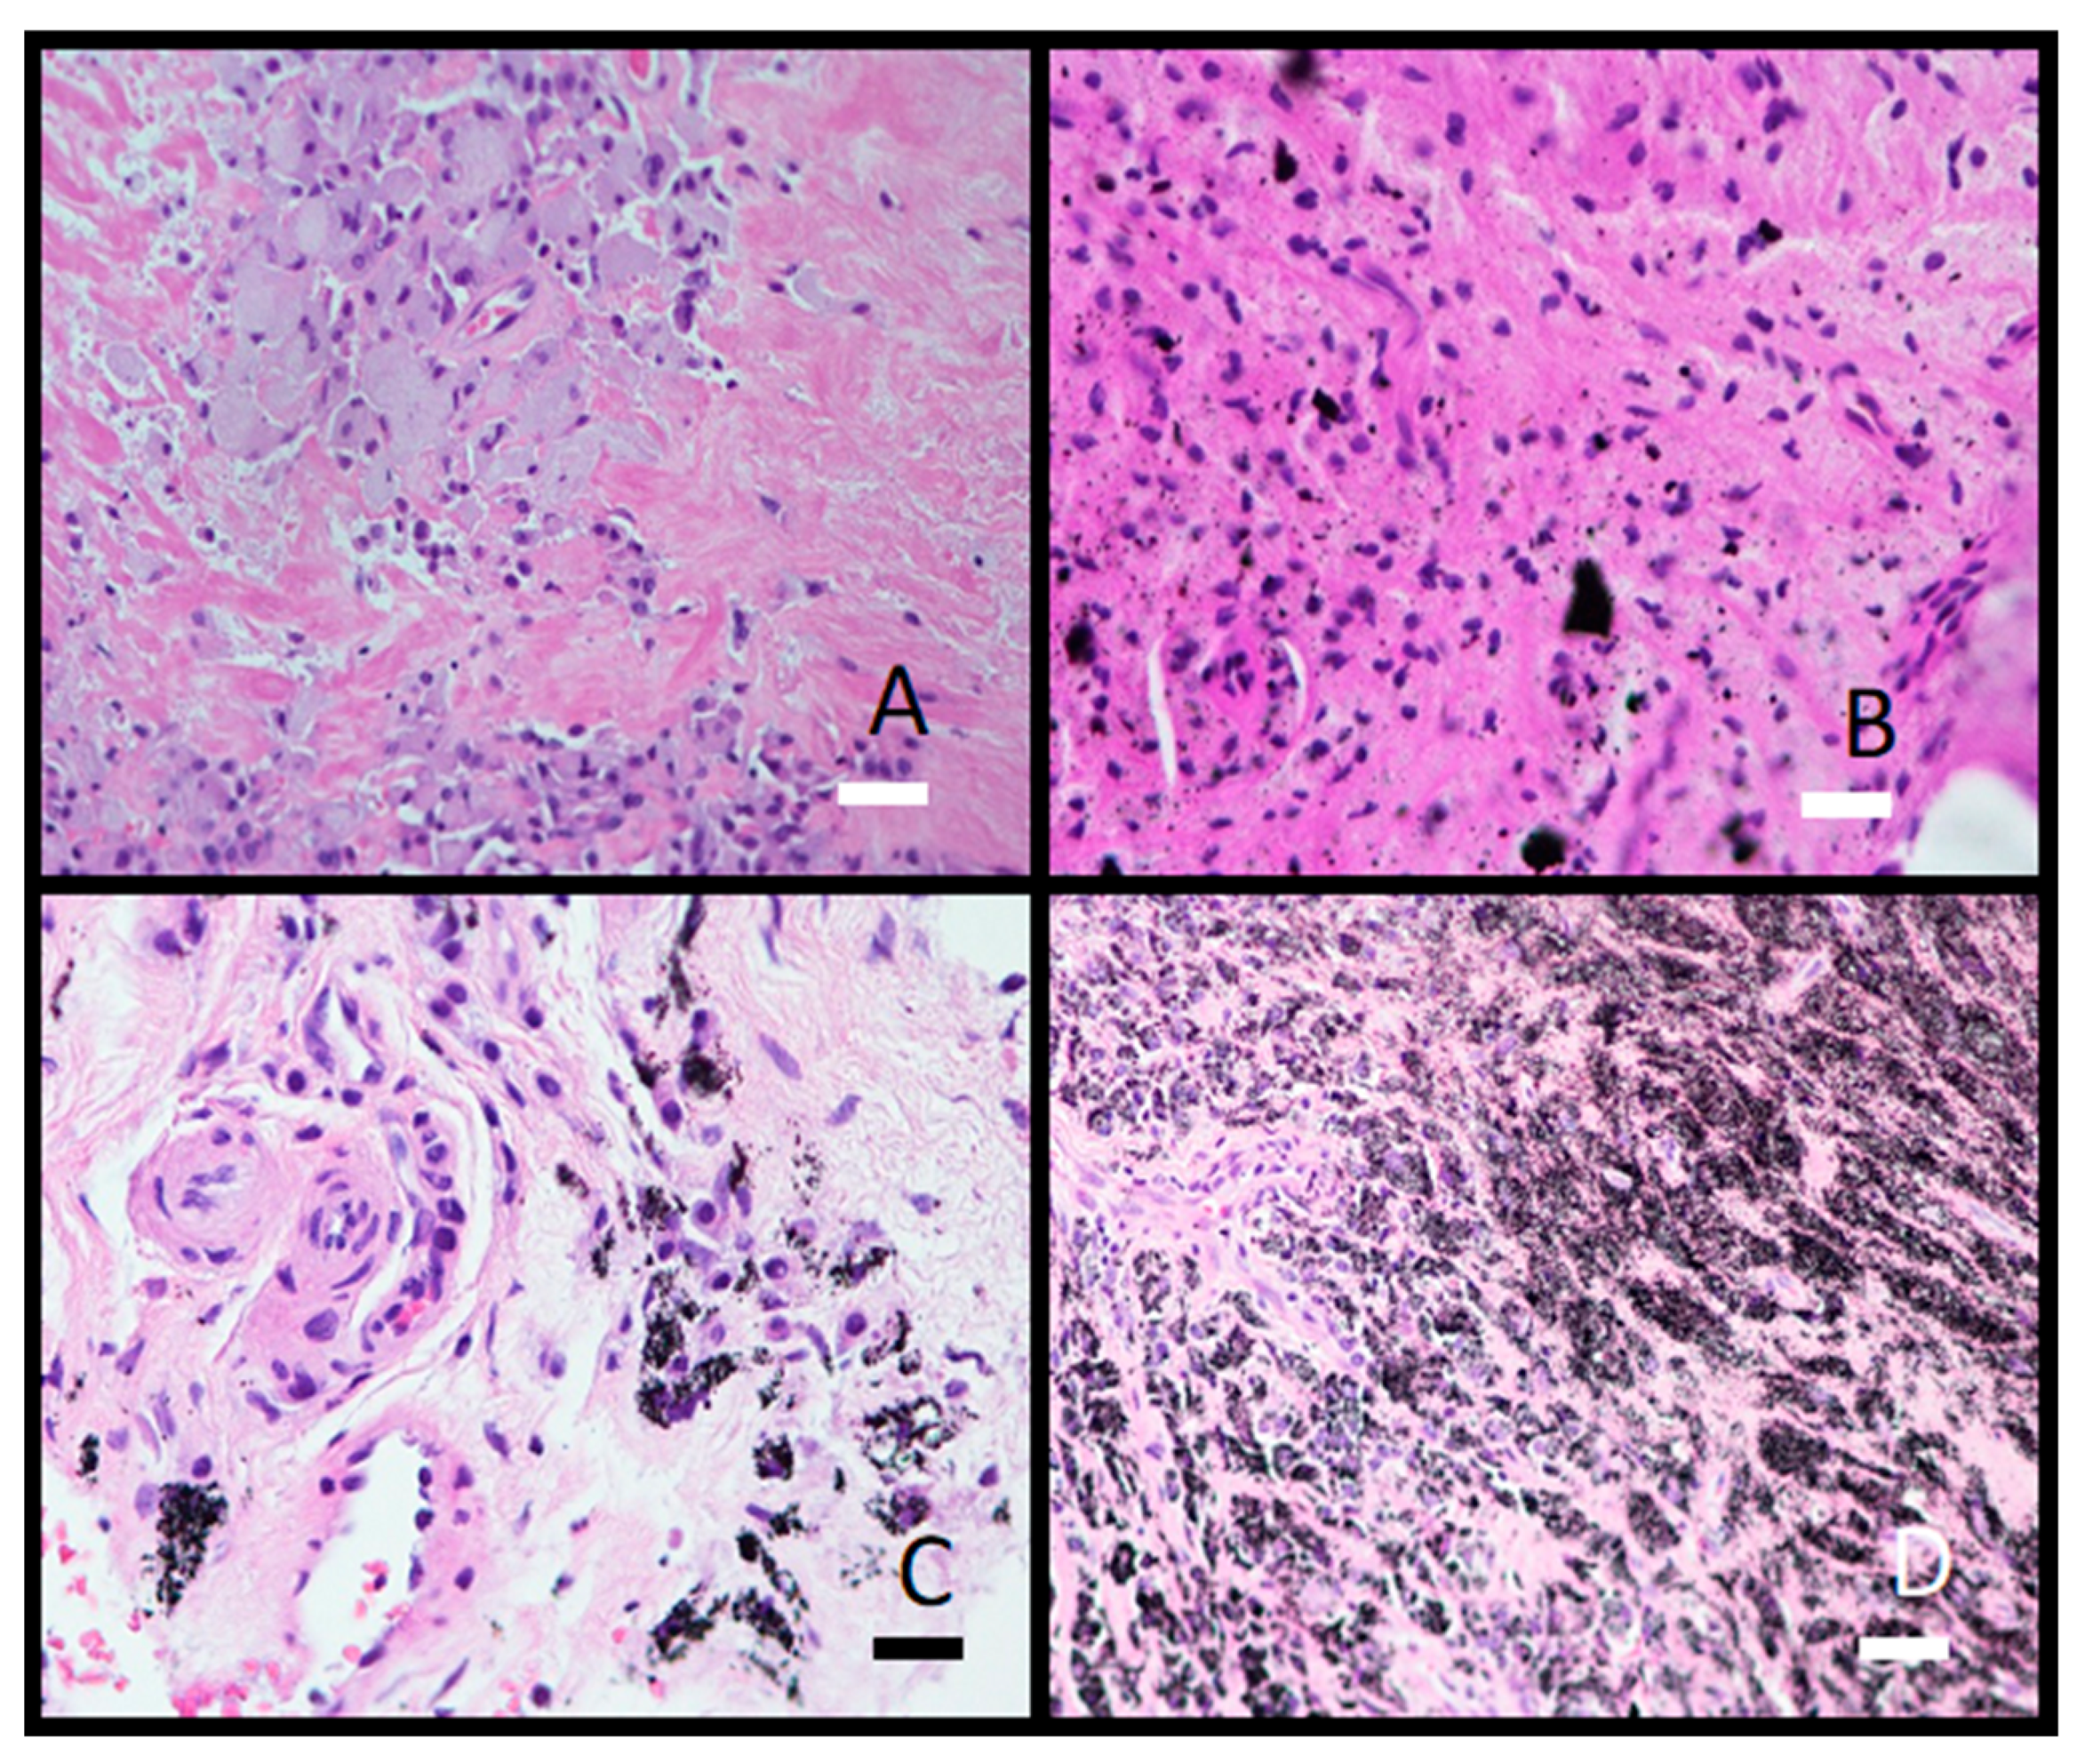

Histological analysis showed granulomatous tissue in a periprosthetic membrane (bone marrow) with macrophages and giant cells. Macrophages contained varying amounts of metal particles in the cytoplasm, which appeared as a grey-blue staining of the cytoplasm or visible black particles (Figure 9). In one case, severe metallosis was found. Besides macrophages and giant cells, lymphocyte infiltration was seen as diffuse infiltration or as small perivascular cuffs (Figure 10).

Figure 9.

Photomicrographs of granulomatous tissue from a periprosthetic membrane filled with macrophages containing metal wear particles. (A) Gray-blue macrophage cytoplasm (obj. mag. 20×); (B) Black, needle-shaped to polygonal, sharp-edged metal microparticles different in size (obj. mag. 20×); (C) Cytoplasm filled with black particles (obj. mag. 40×); (D) Severe metallosis with metal particles in macrophages and extracellular space (obj. mag. 20×). Black bar = 50 μm and white bars = 100 μm.

We were the first to discover that besides implant surfaces, the contamination extends into the subsurface down to 30 μM [16,19,20]. Hard Al2O3 debris particles (Mosh Scale 9) embed into the soft matrix of Ti6Al7Nb (alpha+ beta) alloy, causing the cracks to spread to the surface. The cracks are potential places for bacteria adhesion and consequently implant infection. Wear debris (metallic, polymeric, and corundum (Al2O3)) causes inflammation of the soft tissue near the hip endoprosthesis. We found Al2O3 particles in the soft tissue as determined with histopathology analysis (Figure 9 and Figure 10). The material was not cytotoxic; however, it impacted the growth of the cells.